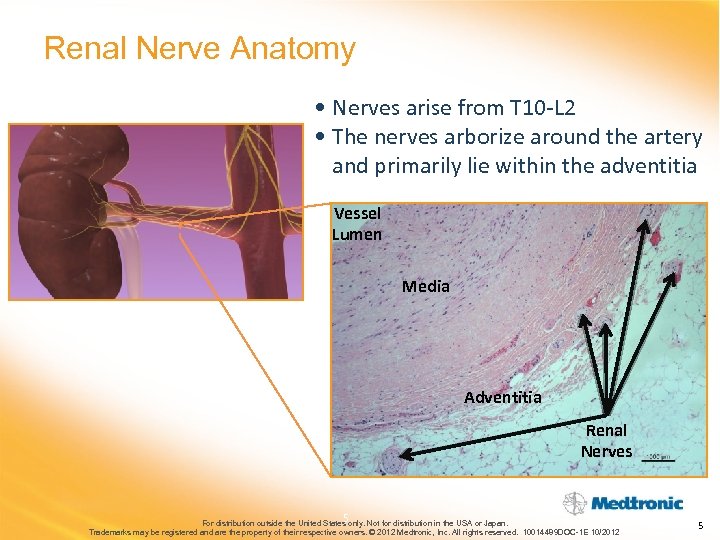

Renal Nerve Anatomy • Nerves arise from T 10 -L 2 • The nerves arborize around the artery and primarily lie within the adventitia Vessel Lumen Media Adventitia Renal Nerves 5 For distribution outside the United States only. Not for distribution in the USA or Japan. Trademarks may be registered and are the property of their respective owners. © 2012 Medtronic, Inc. All rights reserved. 10014489 DOC-1 E 10/2012 5

Renal Nerve Anatomy • Nerves arise from T 10 -L 2 • The nerves arborize around the artery and primarily lie within the adventitia Vessel Lumen Media Adventitia Renal Nerves 5 For distribution outside the United States only. Not for distribution in the USA or Japan. Trademarks may be registered and are the property of their respective owners. © 2012 Medtronic, Inc. All rights reserved. 10014489 DOC-1 E 10/2012 5